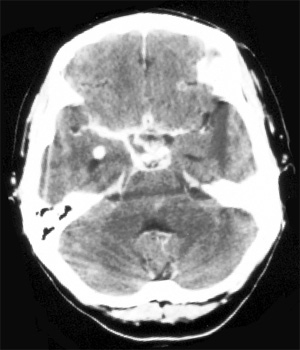

Head CT > Infection > Meningitis

Meningitis

There are three subtypes of meningitis. Acute pyogenic meningitis is usually bacterial. Lymphocytic meningitis is usually viral, benign and self-limited. Chronic meningitis is often seen in immunocompromised hosts and may be fungal or parasitic. Imaging in suspected meningitis patients is performed to look for complications and assess safety of lumbar puncture. Imaging is not usually performed to diagnose meningitis because imaging studies are frequently normal despite the presence of the disease.